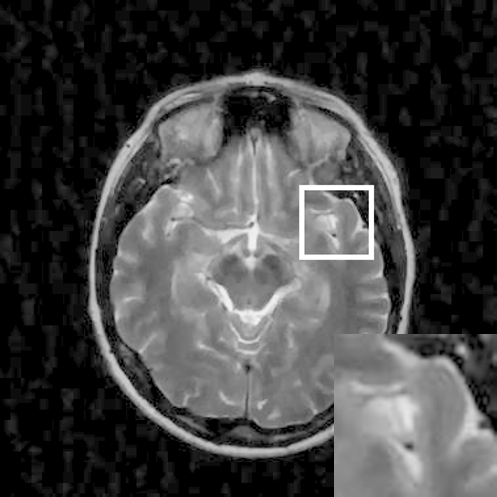

Figure 9: Reconstruction results for 30% radial sampling. (a) Original. (b)-(h) Reconstructed images. (i)-(n) The errors of six CSMRI methods.

As shown in Figs. 7, 8 and 9, Sparse MRI and DLMRI have a lot of unpleasant artifacts, Residual learning and U-net can eliminate most of artifacts, but are not ideal for restoring image details. However, the proposed method can reconstruct better MR images, which outperforms other competitive methods in visualization of structures reconstruction and artifacts removal. Meanwhile, we can see from the absolute error residuals for three sampling experiments that the proposed MDN algorithm restores a finer detail structure than other algorithms. Moreover, we present the PSNR and SSIM values in Table I for different algorithms, sampling masks and sampling rates. It is demonstrated that the proposed method provides better reconstruction performance and visual results than other competitive methods. We can also see the obvious improvement of all algorithms over zero-filling both in visualization. In particular, a higher SSIM value of Sparse MRI appears when using 30% variable density random sampling, however, Sparse MRI generates more artifacts than the proposed MDN.